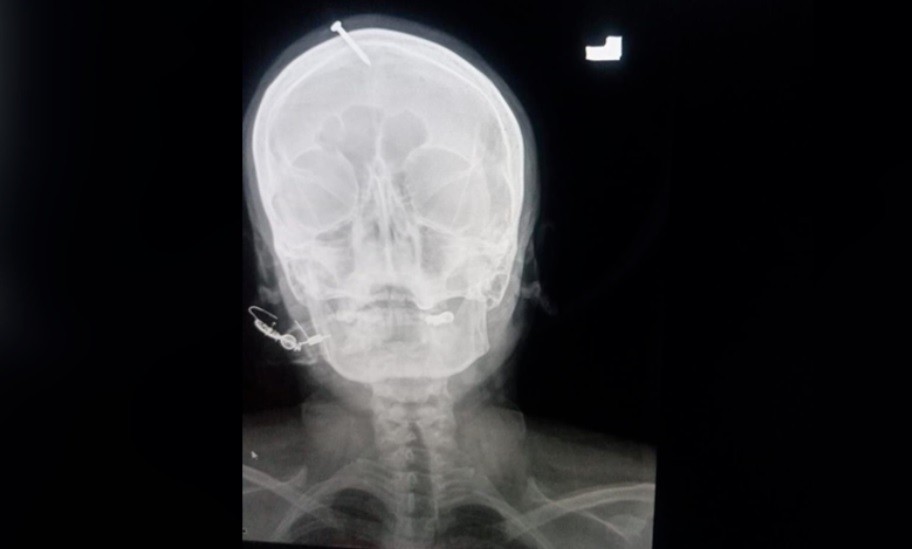

Una mujer embarazada se presentó en un hospital pakistaní con un clavo clavado en la cabeza por un curandero que le había garantizado que así daría a luz a un niño, informaron el miércoles fuentes médicas.

Una radiografía mostró que el clavo había sido clavado cinco centímetros en el cráneo, sin llegar al cerebro.